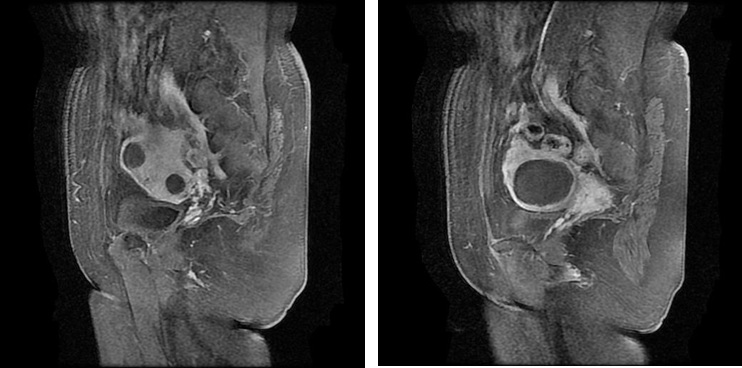

图片

MRI显示:子宫多发肌瘤

2. 盆腔增强(3T):子宫形态不规则,浆膜下、肌层及粘膜下多发(10枚左右)类圆形结节、肿块影,大部分呈等T1短T2信号影,最大者呈等T1略长T2信号,大小约7.9×7.0cm,其内信号不均,增强扫描轻-中度不均匀强化,相邻宫腔受压变形。宫颈部多发小囊样异常信号,大者约0.6cm,无明显强化。阴道未见明显异常。膀胱充盈尚可,壁不厚。直肠抠未见异常改变。盆腔内未见明显肿大淋巴结影。